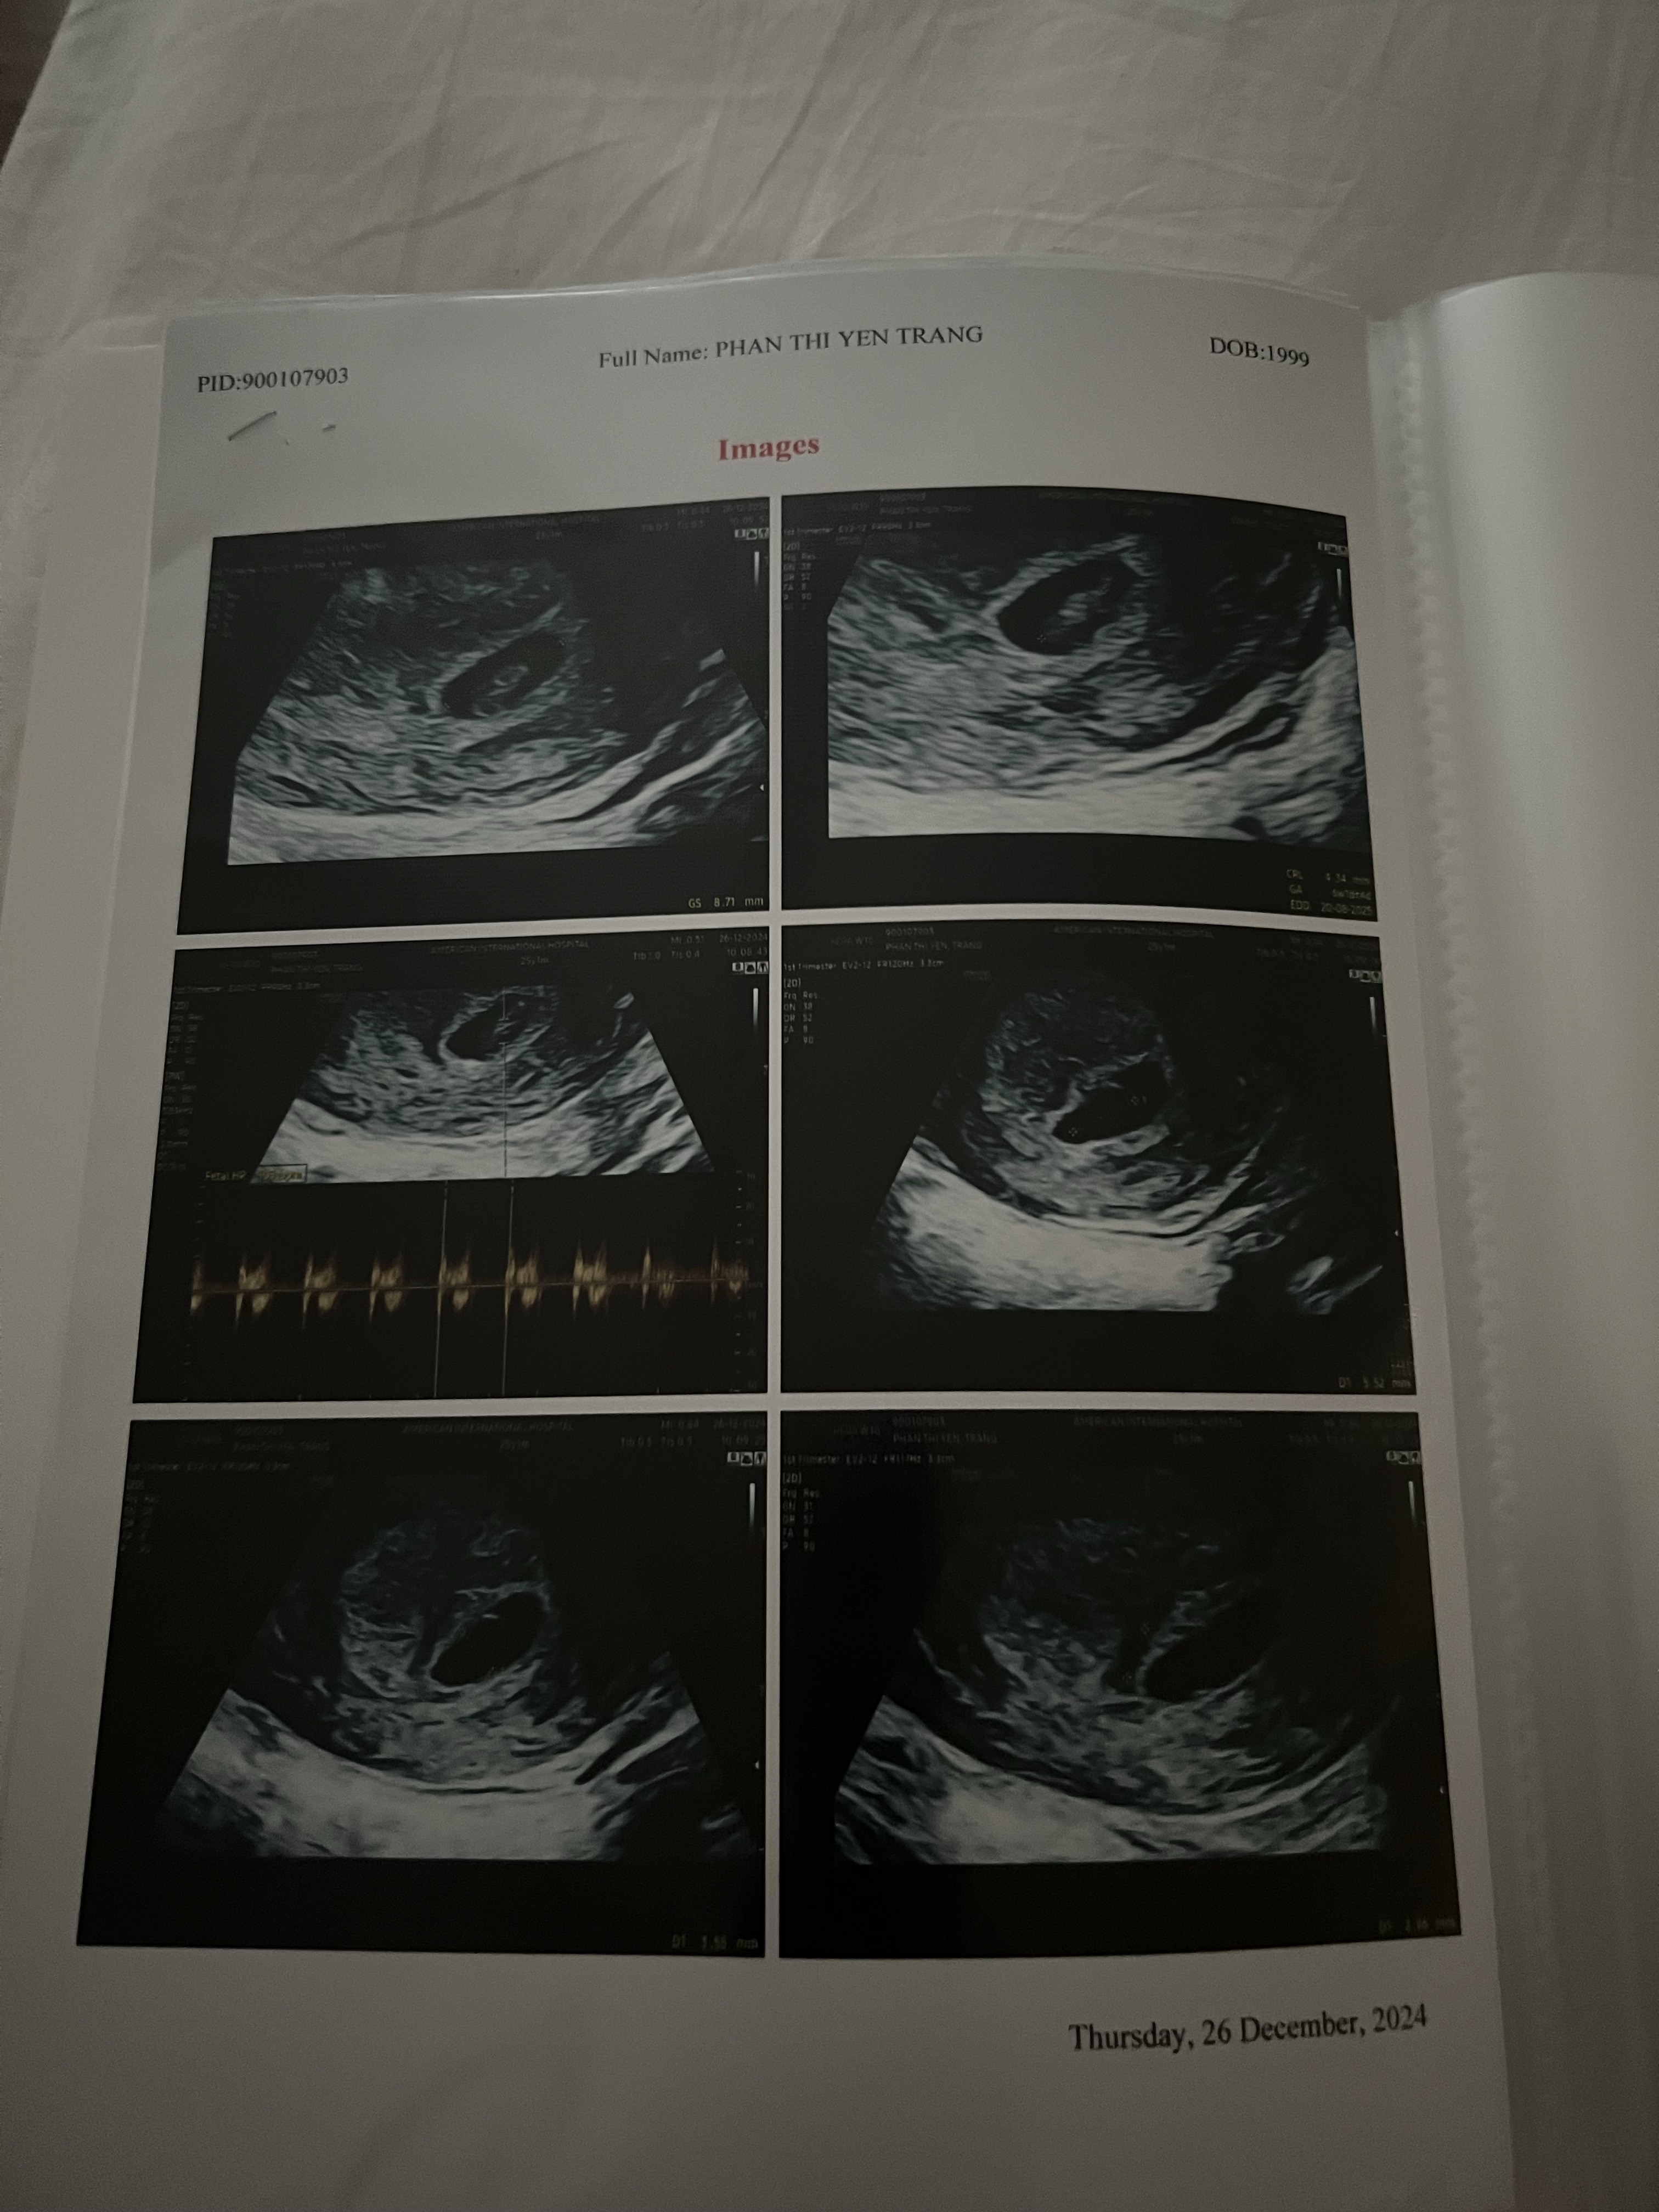

Thai nhi có noãn hoàng 5.5mm 6w

Bé của em có kết quả siêu âm trên , bé có cơ hội được khoẻ mạnh bình thường không ạ em lo lắng quá